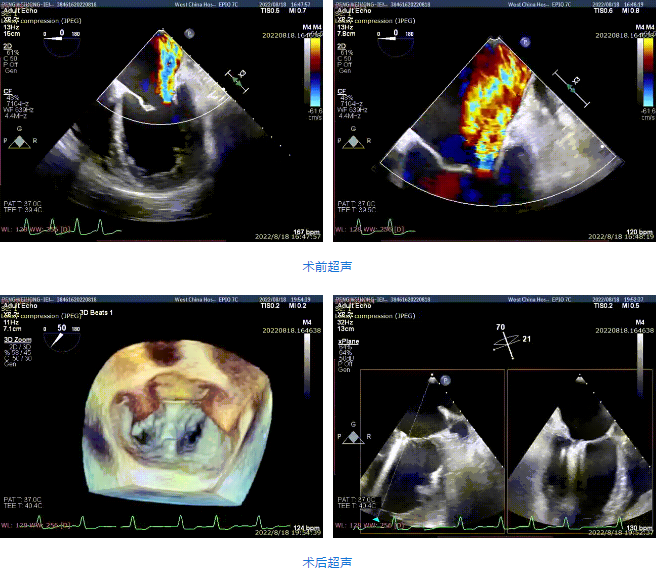

接受治療的是一例59歲男性患者,主訴“心累氣促5余年,加重伴胸痛1個多月”,已經過規范化藥物治療。術前超聲提示左心明顯增大,右心稍大。左室心尖部肌小梁增多。室間隔及左室后壁厚度正常,左室后下壁基底段變薄、稍向外膨出,搏幅明顯減弱,余室壁搏幅減低,左室壁整體運動欠協調。二尖瓣瓣尖稍增厚,回聲稍增強,后瓣受牽拉,活動度差,前瓣關閉錯位,開放尚可。多普勒提示:二尖瓣大量反流(VC=6*18mm,EOA=0.53cm2,Vol=61ml);二尖瓣環舒張期運動頻譜呈單峰,EF=30%。

手術采用全身麻醉插管,經股靜脈-房間隔入路,在TEE和DSA引導下完成房間隔穿刺。置入瓣膜夾系統后,在左房調整瓣膜夾的位置和軸向,后進入左室,在TEE引導下捕捉二尖瓣前后瓣葉,并關閉瓣膜夾。經TEE反復確認手術效果后最終鎖定并釋放瓣膜夾。術后即刻超聲顯示瓣膜夾位置穩定,功能良好,肺靜脈逆流和左房壓都明顯好轉。